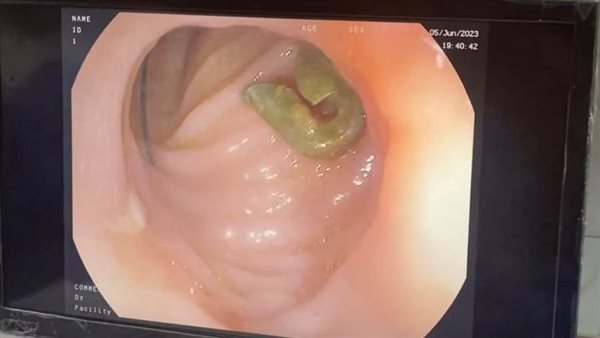

واستقبل المستشفى طفل يبلغ من العمر 7 أشهر، بعد ابتلاعه "دبوس" مشبك مفتوح، وقد بينت الأشعة وجود الجسم المعدني في الجزء الأول من الإثنى عشر، وقد انغرس طرفه المدبب في جدار الأمعاء.

وبعد توقيع الكشف الطبي على الحالة، تبين أن الحل الأمثل هو استخراج الدبوس عن طريق المنظار، والذي يحتاج إلى مهارة عالية جدا نظرًا لصغر عمر المريض، ووجوده مفتوحًا ومنغرس طرفه في جدار الأمعاء، أو إجراء عملية جراحية للرضيع.

وتمكن الفريق الطبي من استخراج الجسم المعدني عبر المنظار دون حدوث أي مضاعفات، وذلك تحت إشراف الدكتور محمد عز، استاذ طب الأطفال رئيس وحدة الجهاز الهضمي، والدكتورة إسراء زينهم، مدرس مساعد طب الأطفال، والدكتور مصطفى العيوطي، مدرس جراحة الأطفال، والدكتور آية منير، نائب التخدير، وناجي محفوظ، فني المناظير، والتمريض فاطمة محمد.